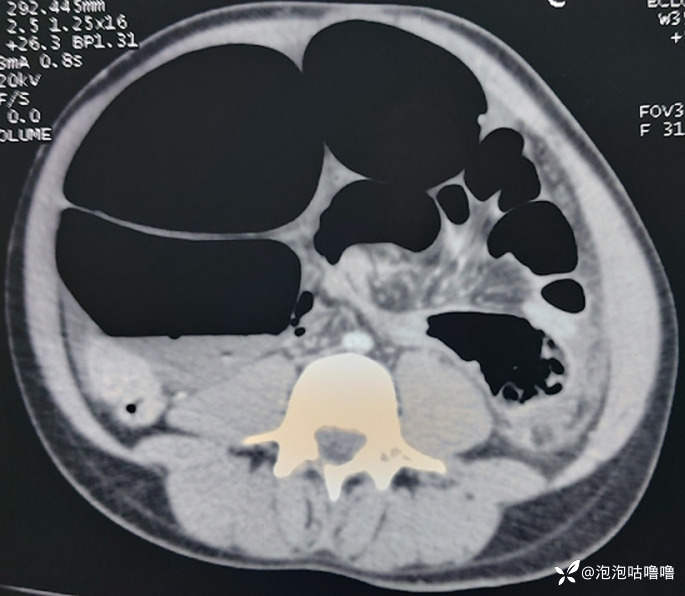

入院查体情况:神情焦虑、乏力,呼吸急促、心动过速(心率151次/分钟),血压70/50 mmHg。触诊时腹部膨大、压痛、有鼓室感,直肠指诊时可见游离疝口和空壶腹。血液检查显示血浆 C 反应蛋白水平增至 106.3 mg/L,急性肾功能不全,肌酐为 23.8 mg/L,碳酸氢盐为 17.6mmol/L。腹部X线检查显示大肠明显扩张,咖啡豆征,气液平。腹部CT 扫描:乙状结肠发生旋转和显着扩张,直径为 12 厘米,顶叶变薄(图1)。

腹部 CT 扫描显示乙状结肠有旋转和明显扩张,直径为 12 厘米,顶叶变薄。